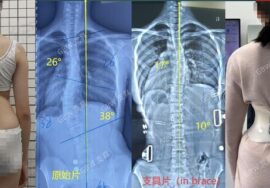

الحالات المتوسطة: استخدام الأحزمه الطبيه

الأشعة السينية: لتحديد درجة الانحناء (زاوية كوب).

الأحزمه الطبية (مثل PioBrace): فعالة عند الأطفال.

أحدث التقنيات العالمية: نعتمد على تقنيات حديثة مثل أجهزة التقييم الدقيقة وأحزمة التقويم المتقدمة مثل PioBrace.